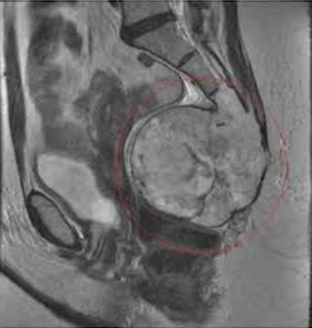

- Родовые повреждения – редкий вид патологии. Физиологически при робах крестец должен отклоняться назад. Если на рентгене или МРТ видна сгибательная деформация крестце (внутрь), то это никак не может быть родовым повреждением.

- Магнитно-резонансная томография. Получение полной информации о костных и мягких тканях. Позволяет исключить опухоли.